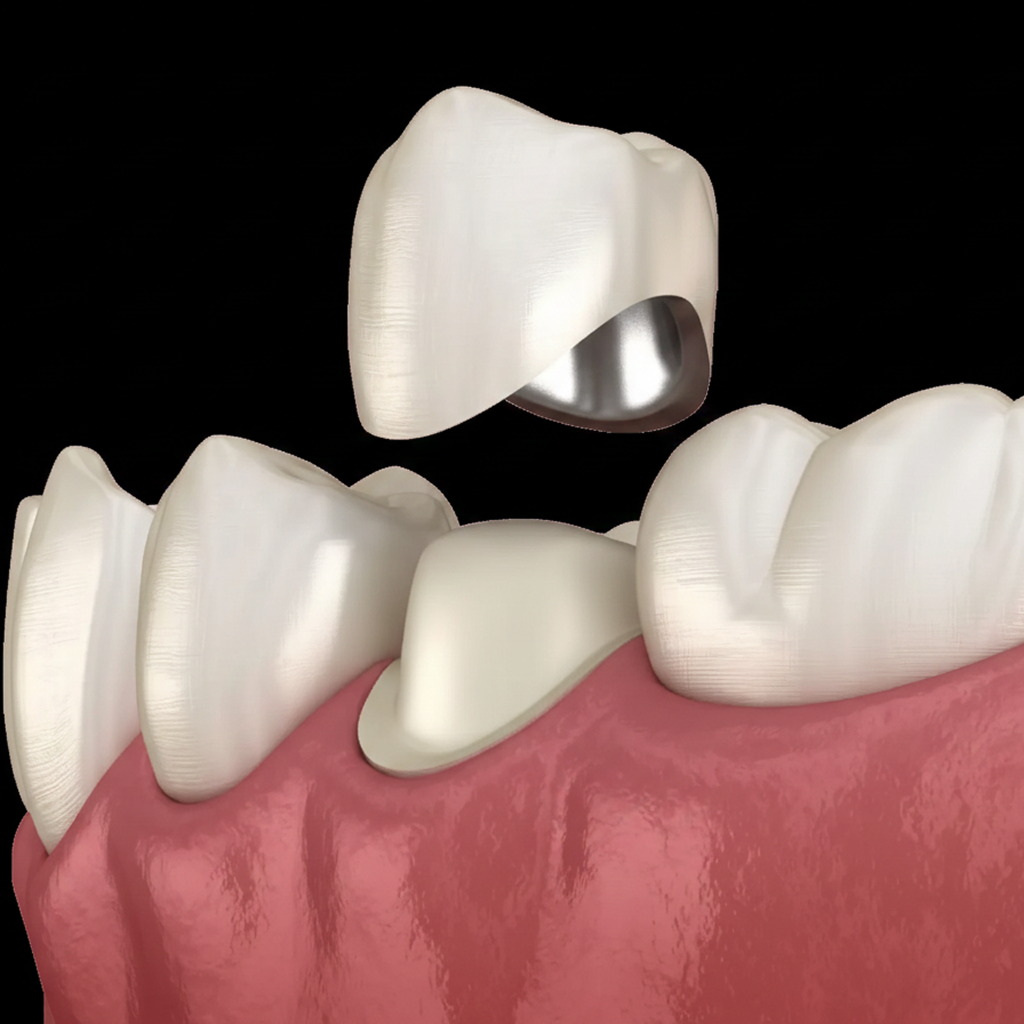

Coroană metalo-ceramică pe dinte

(aprox. 150 euro)

- Bază din Aliaj Metalic Biocompatibil

- Înveliș Ceramic cu Aspect Natural

- Protecție Ridicată pentru Dinții Devitalizați

- Etanșare Marginală pentru Prevenirea Cariilor

- Durabilitate Clasică la un Preț Accesibil